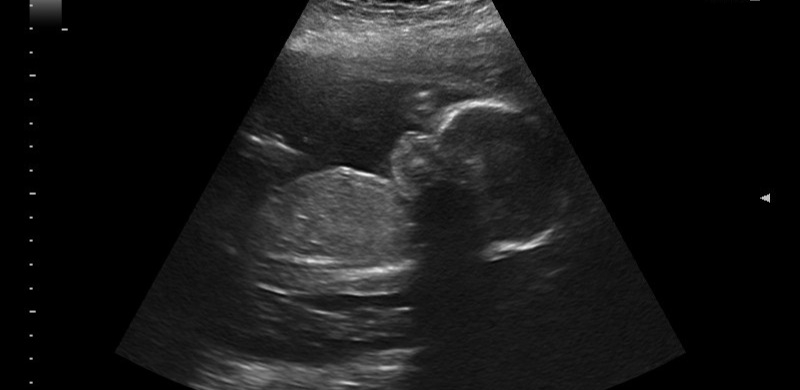

Well I had an ultrasound today but no new pictures. Baby was lying facedown on the placenta with an arm over its face and refused to turn. The tech managed to get about half of the measurements she needed. Good news is that means I get an extra ultrasound in two weeks to try and get the rest of the measurements. From there, no more scans until 32 weeks so I'll probably be worried the entire time 👍

Our boy was much more cooperative today! Managed to get all the measurements we needed and everything looks good. It looks like he's a bit on the bigger side (estimated at 1 lbs 3 oz today), which is funny because I've been concerned that he'll be too small! Got another picture with his hand over his eyes, apparently that's his pose. He moved there right before the tech took the photo.